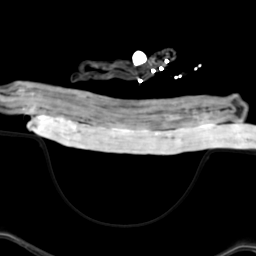

标题: CT16686: 胆总管末端结石

病人手术,术中见结石嵌在壶腹部,部分进入十二指肠,战友可以看看轴扫片第11-13幅,我们也是术后回顾片子才看到。现在把结石影上传,大小约1.5×1.0cm,结石影下方点状高密度影是纱布上的钡丝。